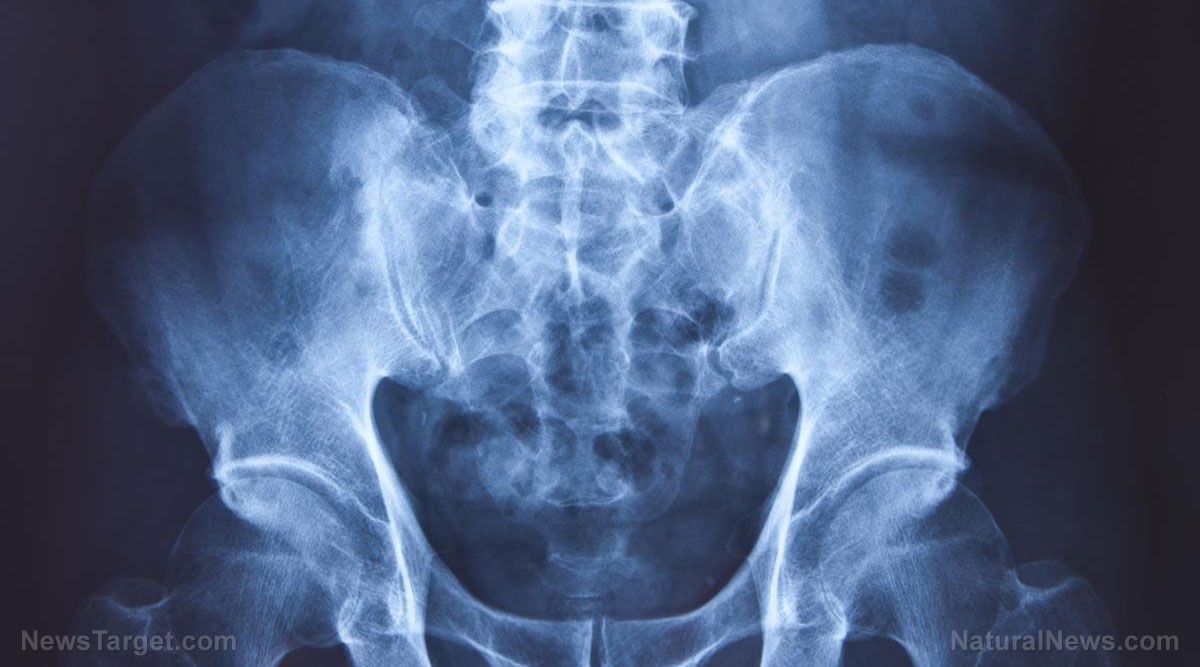

When it comes to healthy bones, people often look to calcium and vitamin D. However, experts suggest adding an unlikely vitamin to the mix: vitamin C. In a recent study published in Osteoporosis International, a team of researchers from Tufts University, Harvard Medical School and the Boston University School of Public Health revealed that taking vitamin C can potentially reduce the likelihood of suffering hip fractures.

The team recorded 100 hip fractures over the follow-up period. Among the participants, those who consumed more vitamin C – whether through food or supplements – had decreased their risk of hip fracture. Those in this group were 44 percent less likely to have a hip fracture than those with a lower intake of the vitamin.

Aside from brittle bones, one of the biggest risks of hip fractures is falling. A sudden shock, like bumping into an object hard, is also a risk. Aside from consuming foods rich in vitamin C, calcium and vitamin D, try the tips below to avoid hip fractures: